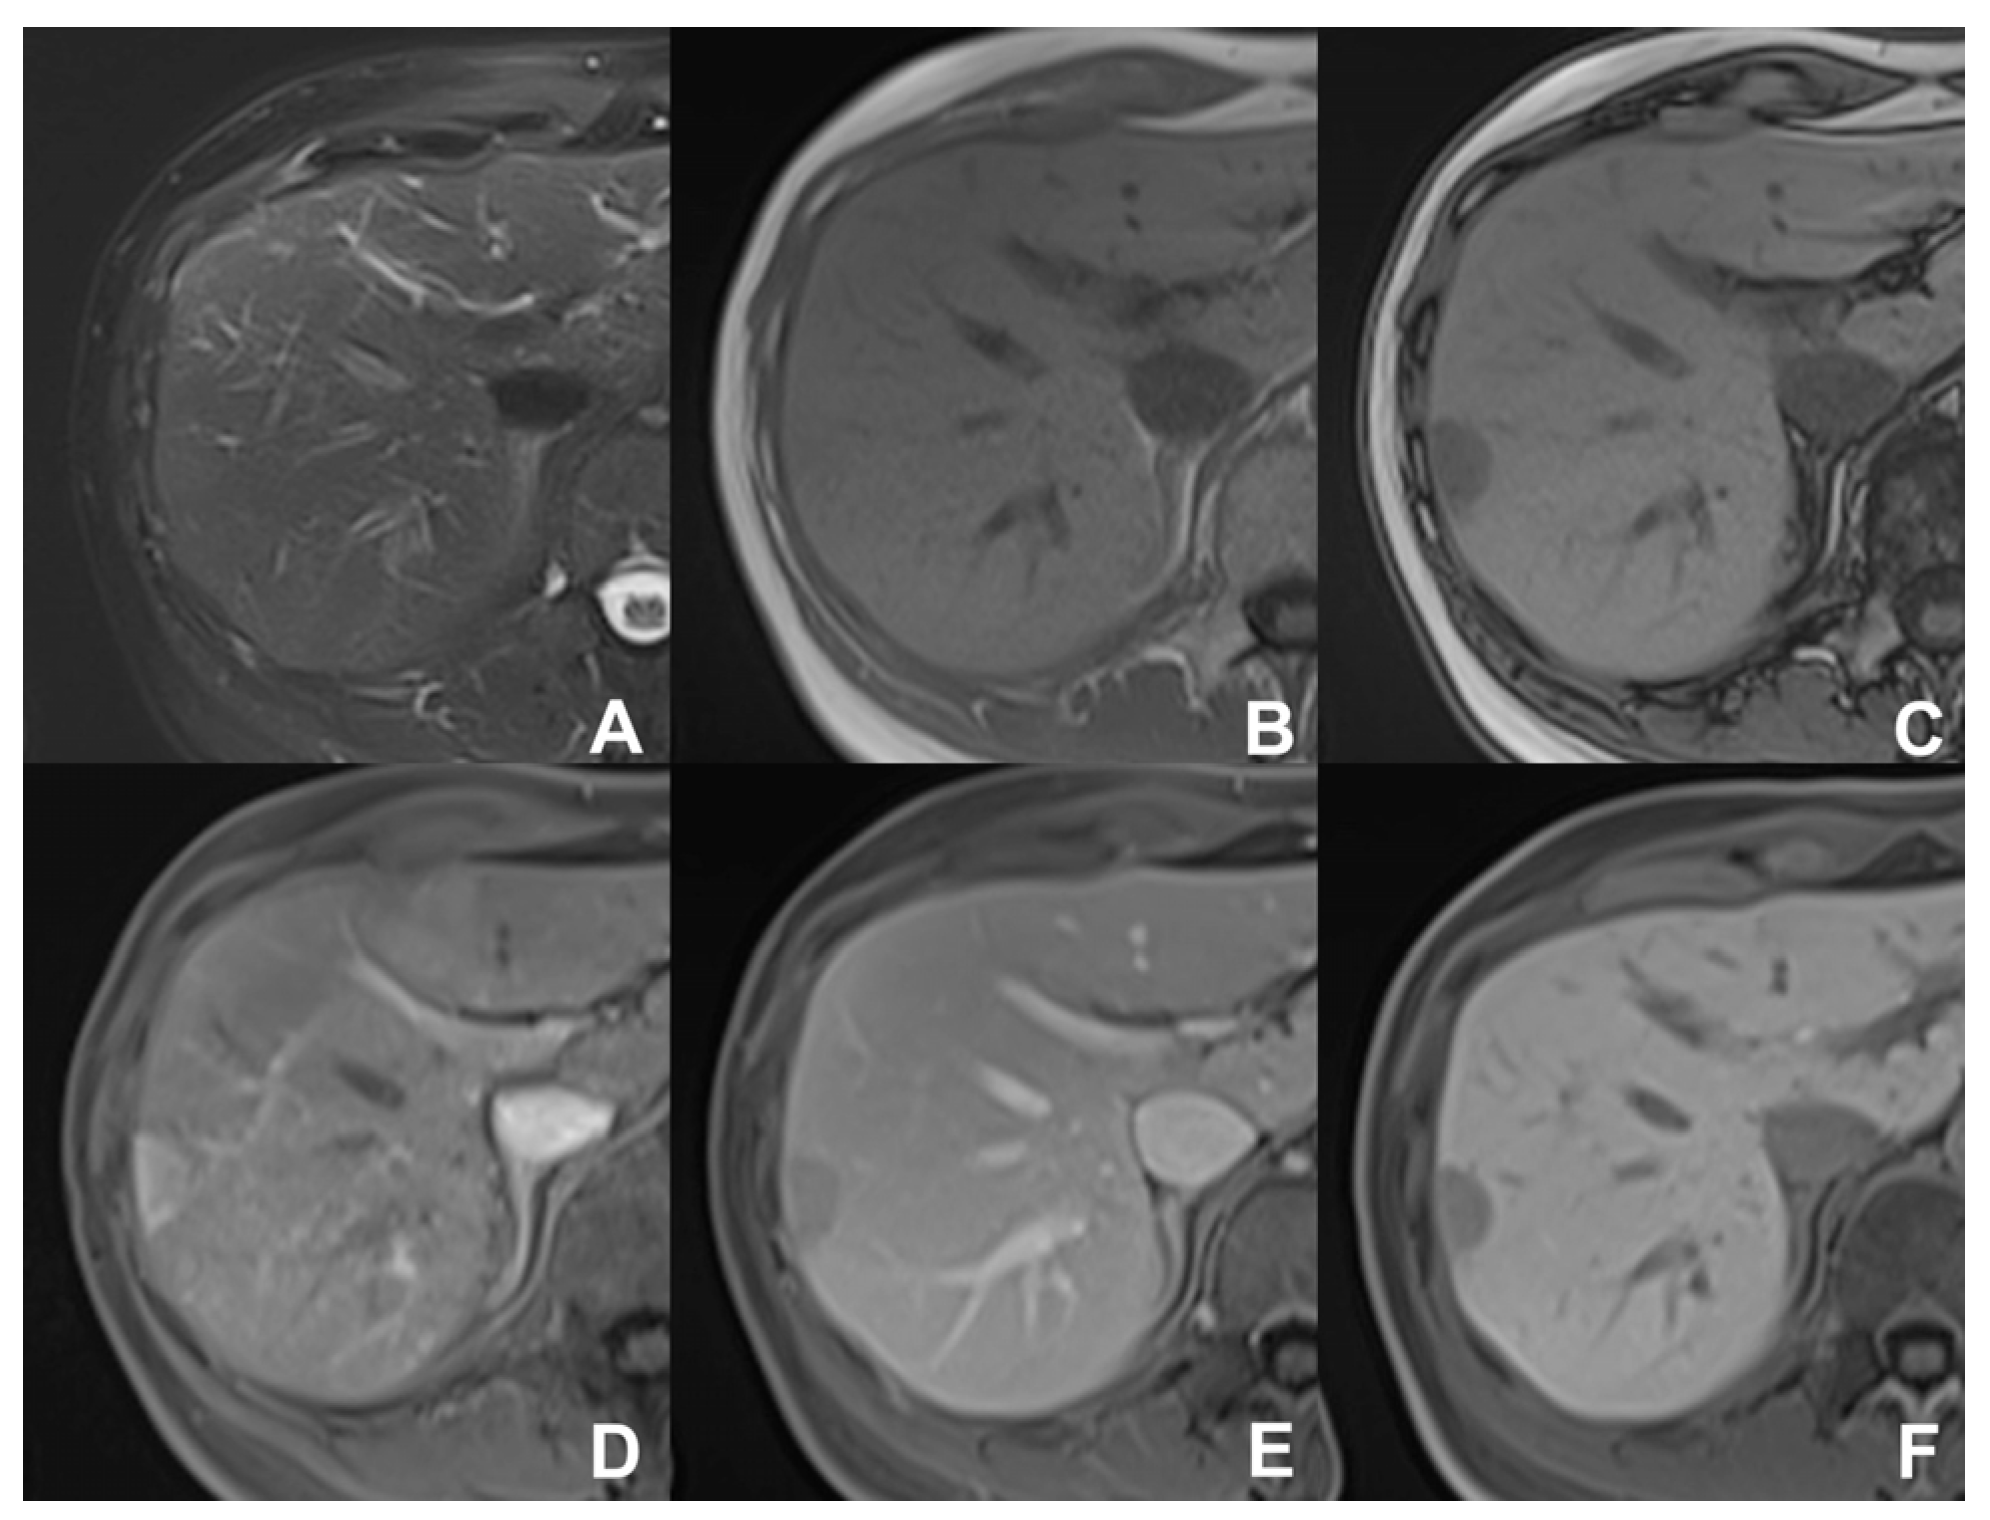

| GRE T1 IN/OUT | AXIAL | -- | -- | Steatosis | |

| GRE T1 3D DYNAMIC | AXIAL | PRE-ART 25″-PORTAL 70″-LATE 180″ | YES (if the lesion is hypervascular) | Benign hypervascular hepatocitic lesions appear hyperintense in HBP | |

| GRE T1 3D DYNAMIC | AXIAL | PRE-ART 25″-PORTAL 70″-LATE 180″ | YES (if the lesion shows atypical enhancement) | Hypointensity in HBP suspicious for HCC | |

| GRE Multi echo | AXIAL | -- | -- | For the quantification of fat and iron content | |